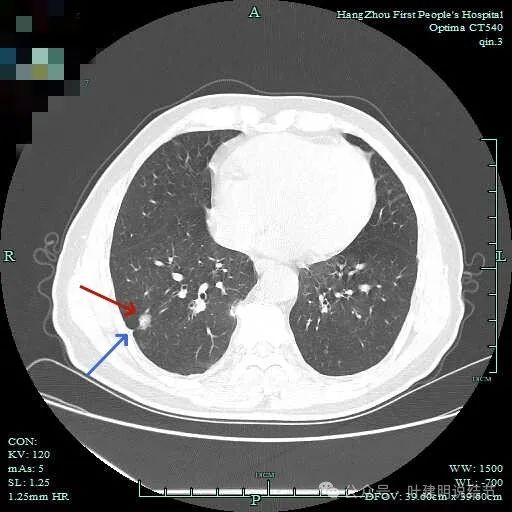

病灶实性伴细毛刺,与脊柱间有间隙在。

病仍明显,从上到下,觉得应该是成片的。

表面不平毛刺,实性密度为主。

微小血管有,但无异常增粗。

病灶实性,边缘不光滑。